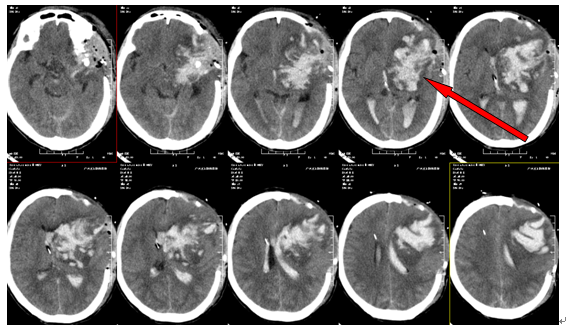

▲术前检查